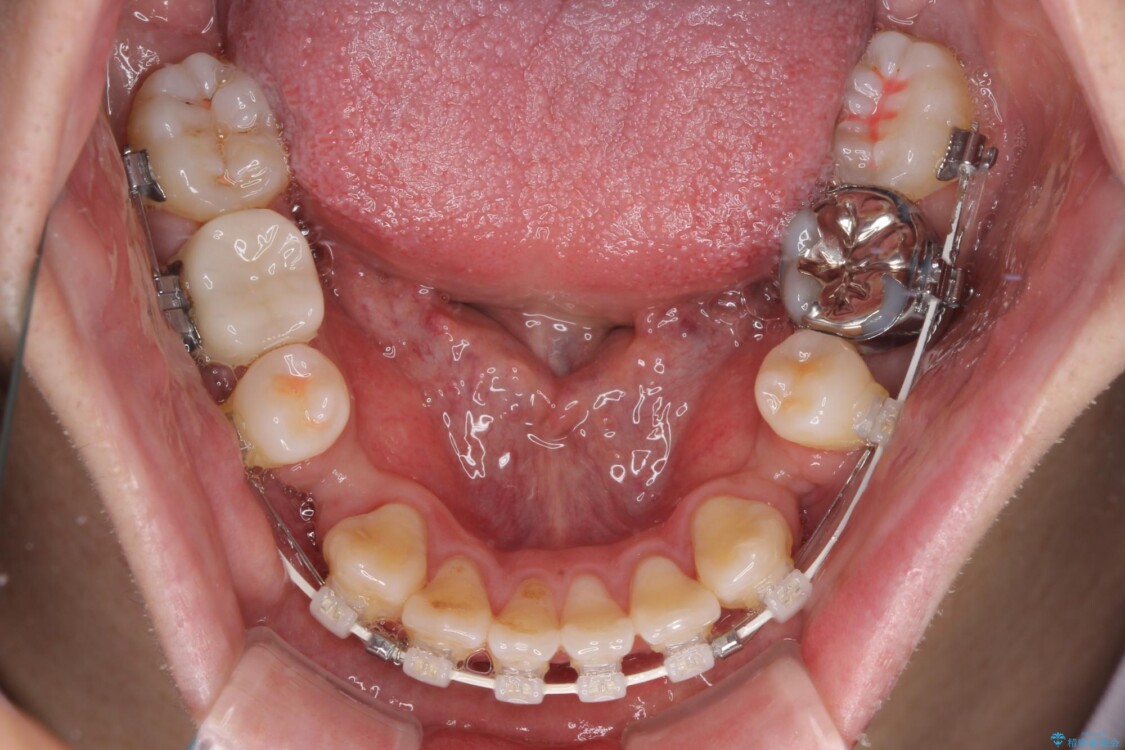

治療途中

• 口元の突出感を改善!目立ちにくいワイヤー矯正で自信を持てる自然な横顔に 治療途中画像

装置は、透明感のあるクリアブラケットとホワイトコーティングされたワイヤーを使用した、目立ちにくい審美装置を選択。

周囲に気づかれにくく、日常生活にも自然に溶け込みます。